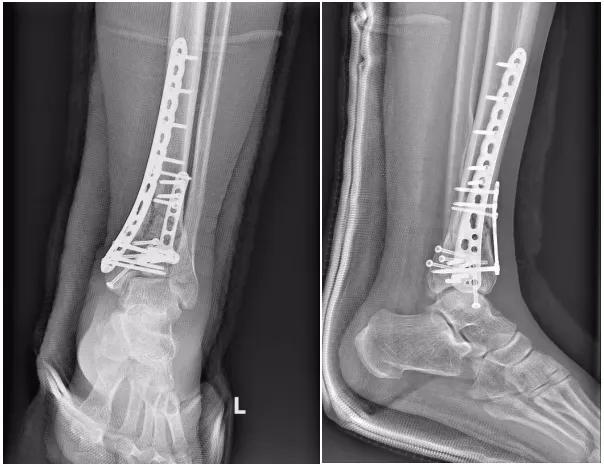

患者被送至医院时,查体见左踝关节严重畸形伴皮肤张力性水疱,足背动脉搏动减弱。医疗团队第一时间为患者安排患肢CT检查,影像结果令人揪心:胫骨远端粉碎性骨折,内踝垂直劈裂骨折,后踝关节面受累骨折,踝关节完全脱位。结合影像学表现与临床症状,确诊为AO/OTA43-C3型Pilon骨折——这是骨科领域公认的“关节骨折治疗天花板”,不仅骨折结构复杂,还伴随软组织高危损伤,稍有延误或处置不当,就可能导致肢体功能障碍甚至截肢风险。

经过7天的精心治疗与观察,患者软组织肿胀逐渐消退,达到手术条件。随即启动多学科协作机制,各团队各司其职、无缝衔接:运动医学科团队术前反复研读CT影像,通过3D建模模拟骨折移位情况,多次开展病例讨论,精准规划复位路径与固定方案,确保手术每一步都“有章可循”;麻醉团队创新采用“腰麻+超声引导下坐骨神经+股神经阻滞”联合麻醉方案,在保证麻醉效果的同时,最大程度减少对患者生理功能的影响;康复团队提前介入,根据患者骨折类型、身体状况,预置个性化术后康复方案,为术后功能恢复提前布局。历经数小时的精细操作,手术顺利完成。